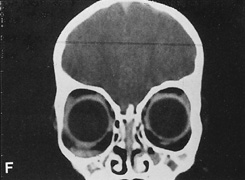

Valuable information about the nature and extent of an orbital pathologic process is provided by imaging studies such as computed tomography (CT) scan, magnetic resonance imaging (MRI), and orbital echography. Better spatial resolution, ready accessibility, and lower cost make CT the preferred choice for orbital imaging in most cases. Orbital fat provides a natural contrast between most adjacent orbital structures on CT scanning, and orbital bones are visualized well. Computed tomography is essential for evaluation of the orbital bones because they cannot be imaged with MRI. Direct coronal or sagittal images are important to identify the relationship of a lesion to the optic nerve so that the surgical approach can be planned to avoid traversing the optic nerve (Fig. 1).

Fig. 1. A. Axial CT scan demonstrating a large, well-encapsulated lesion in the orbital apex. Coronal (B) and sagittal (C) scans demonstrate that the mass lies inferior and medial to the optic nerve within the intraconal space. This information is useful in planning the surgical approach to the mass, which should avoid traversing the optic nerve.